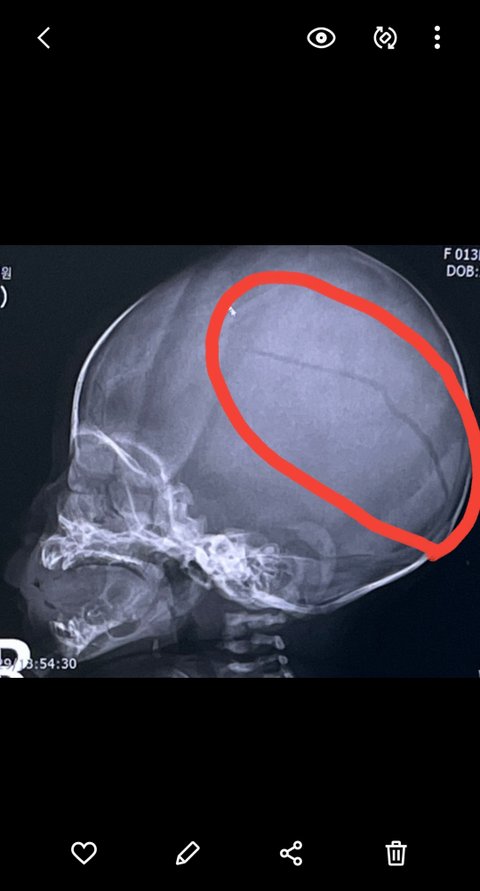

우선 제일 피하고 싶었지만, 안타깝게도 저희 아기 수술을 하였습니다..사고 직후 이미 출혈된 피의 양이 많았고, 성인이였으면 이미 동공확장이나 하체가 마비되는 등의 증상이 나타났을거라고 의사쌤께서 말씀하시더라구요. 그나마 아기가 태어날때 대천문 소천문 같이 뼈들이 열려있어서 출혈로 인한 뇌의 압력을 버텼지만, 병원 입원하고 다음날 찍은 씨티사진을 보니 뇌압이 더 높아져서 대천문쪽 뼈가 더 벌어진 상태더라구요. 아기가 너무 어려서 수술이 조심스럽지만 하지 않을경우 더 안좋아질 가능성이 있어서 교수님들과 협의 끝에 결국 수술을 진행하기로 했습니다.

수술을 마치고 신생아 중환자실로 실려오는 저희 딸을 만났습니다. 그 어린것이 입에 위관호수며 산소호흡기며 주렁주렁 달고 숨쉬고 기침하는 모습이 너무나 괴로워 보였어요. 그 모습을 보며 어제 얼마나 많이 울었는지 모릅니다. 수술전 두개골 깨진 못봤던 CT사진을 보여주셨는데, 저희가 충격받을까봐 정면 사진만 보여주신건지 측면 사진보고 너무 많이 갈라져 있어서 정말 깜짝 놀랐어요. 정신적으로 너무 충격을 많이 받고 몸이 너무 안좋아서 어젯밤 등이 다 젖을 정도로 식은땀 흘려가며 잠을 뒤척였어요. 몸상태가 안좋아서 지금 글을 두서없이 쓴거 같아요..

어제 못봤던 두개골 골절 CT사진.